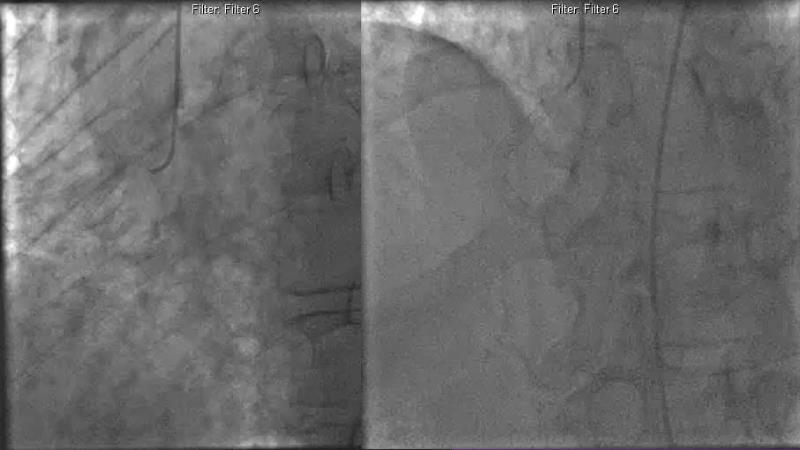

Consult this session to understand the technology and scientific evidence of the novel sirolimus drug-coated balloon, to learn its utility for PCI in a variety of lesion and patient subsets and to understand the evidence and outcomes in real-world patients.

- To understand the evidence and outcomes of this DCB in real world patients